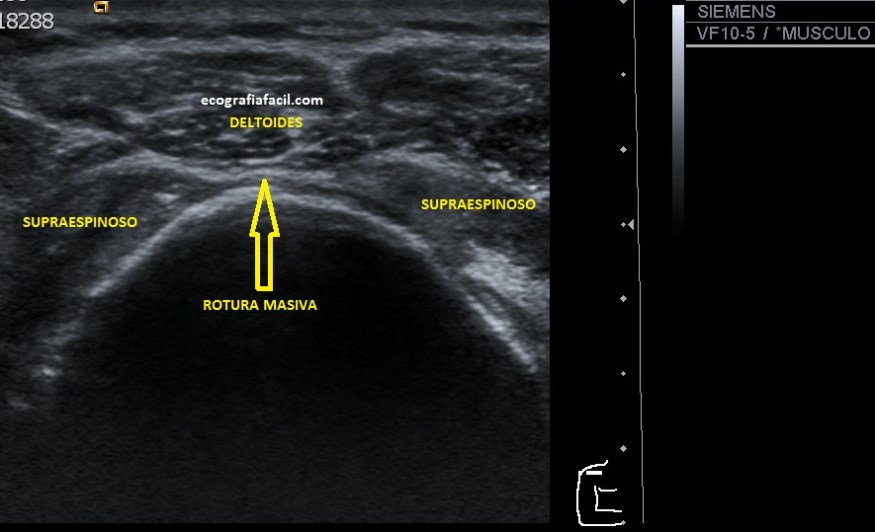

Si tu lo quieres estudiar en un corte transverso o eje corto del tendón verás como muestra de normalidad la imagen número 1. Semiológicamente es muy agradecido. Ves el tendón ovalado, hiperecogénico reposado en la corredera bicipital. El ligamento transverso humeral, hiperecogénico y lineal, anterior a la estructura tendinosa que descansa en la corredera.